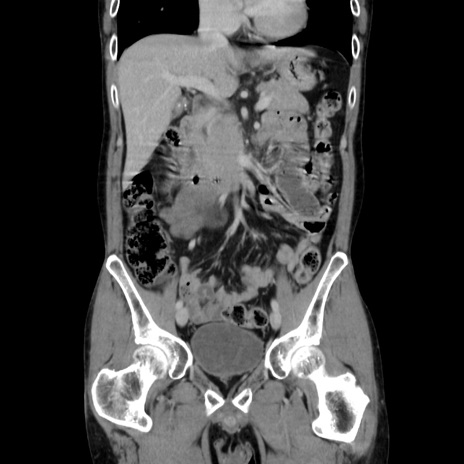

症例37(冠状断像)

【症例】40歳代 男性

【主訴】腹痛

【現病歴】4時間ほど前に電車に乗車中に臍部上より腹痛出現。徐々に増悪し起立困難となり、救急外来受診。生ものは数日食べていない。今朝お雑煮を食べた。

【身体所見】BT 36.8℃、BP 117/84mmHg、HR 91/min、SpO2 97%、苦悶様、腹部:臍上部広範囲圧痛あり、反跳痛±

【データ】WBC 8100、CRP 0.03